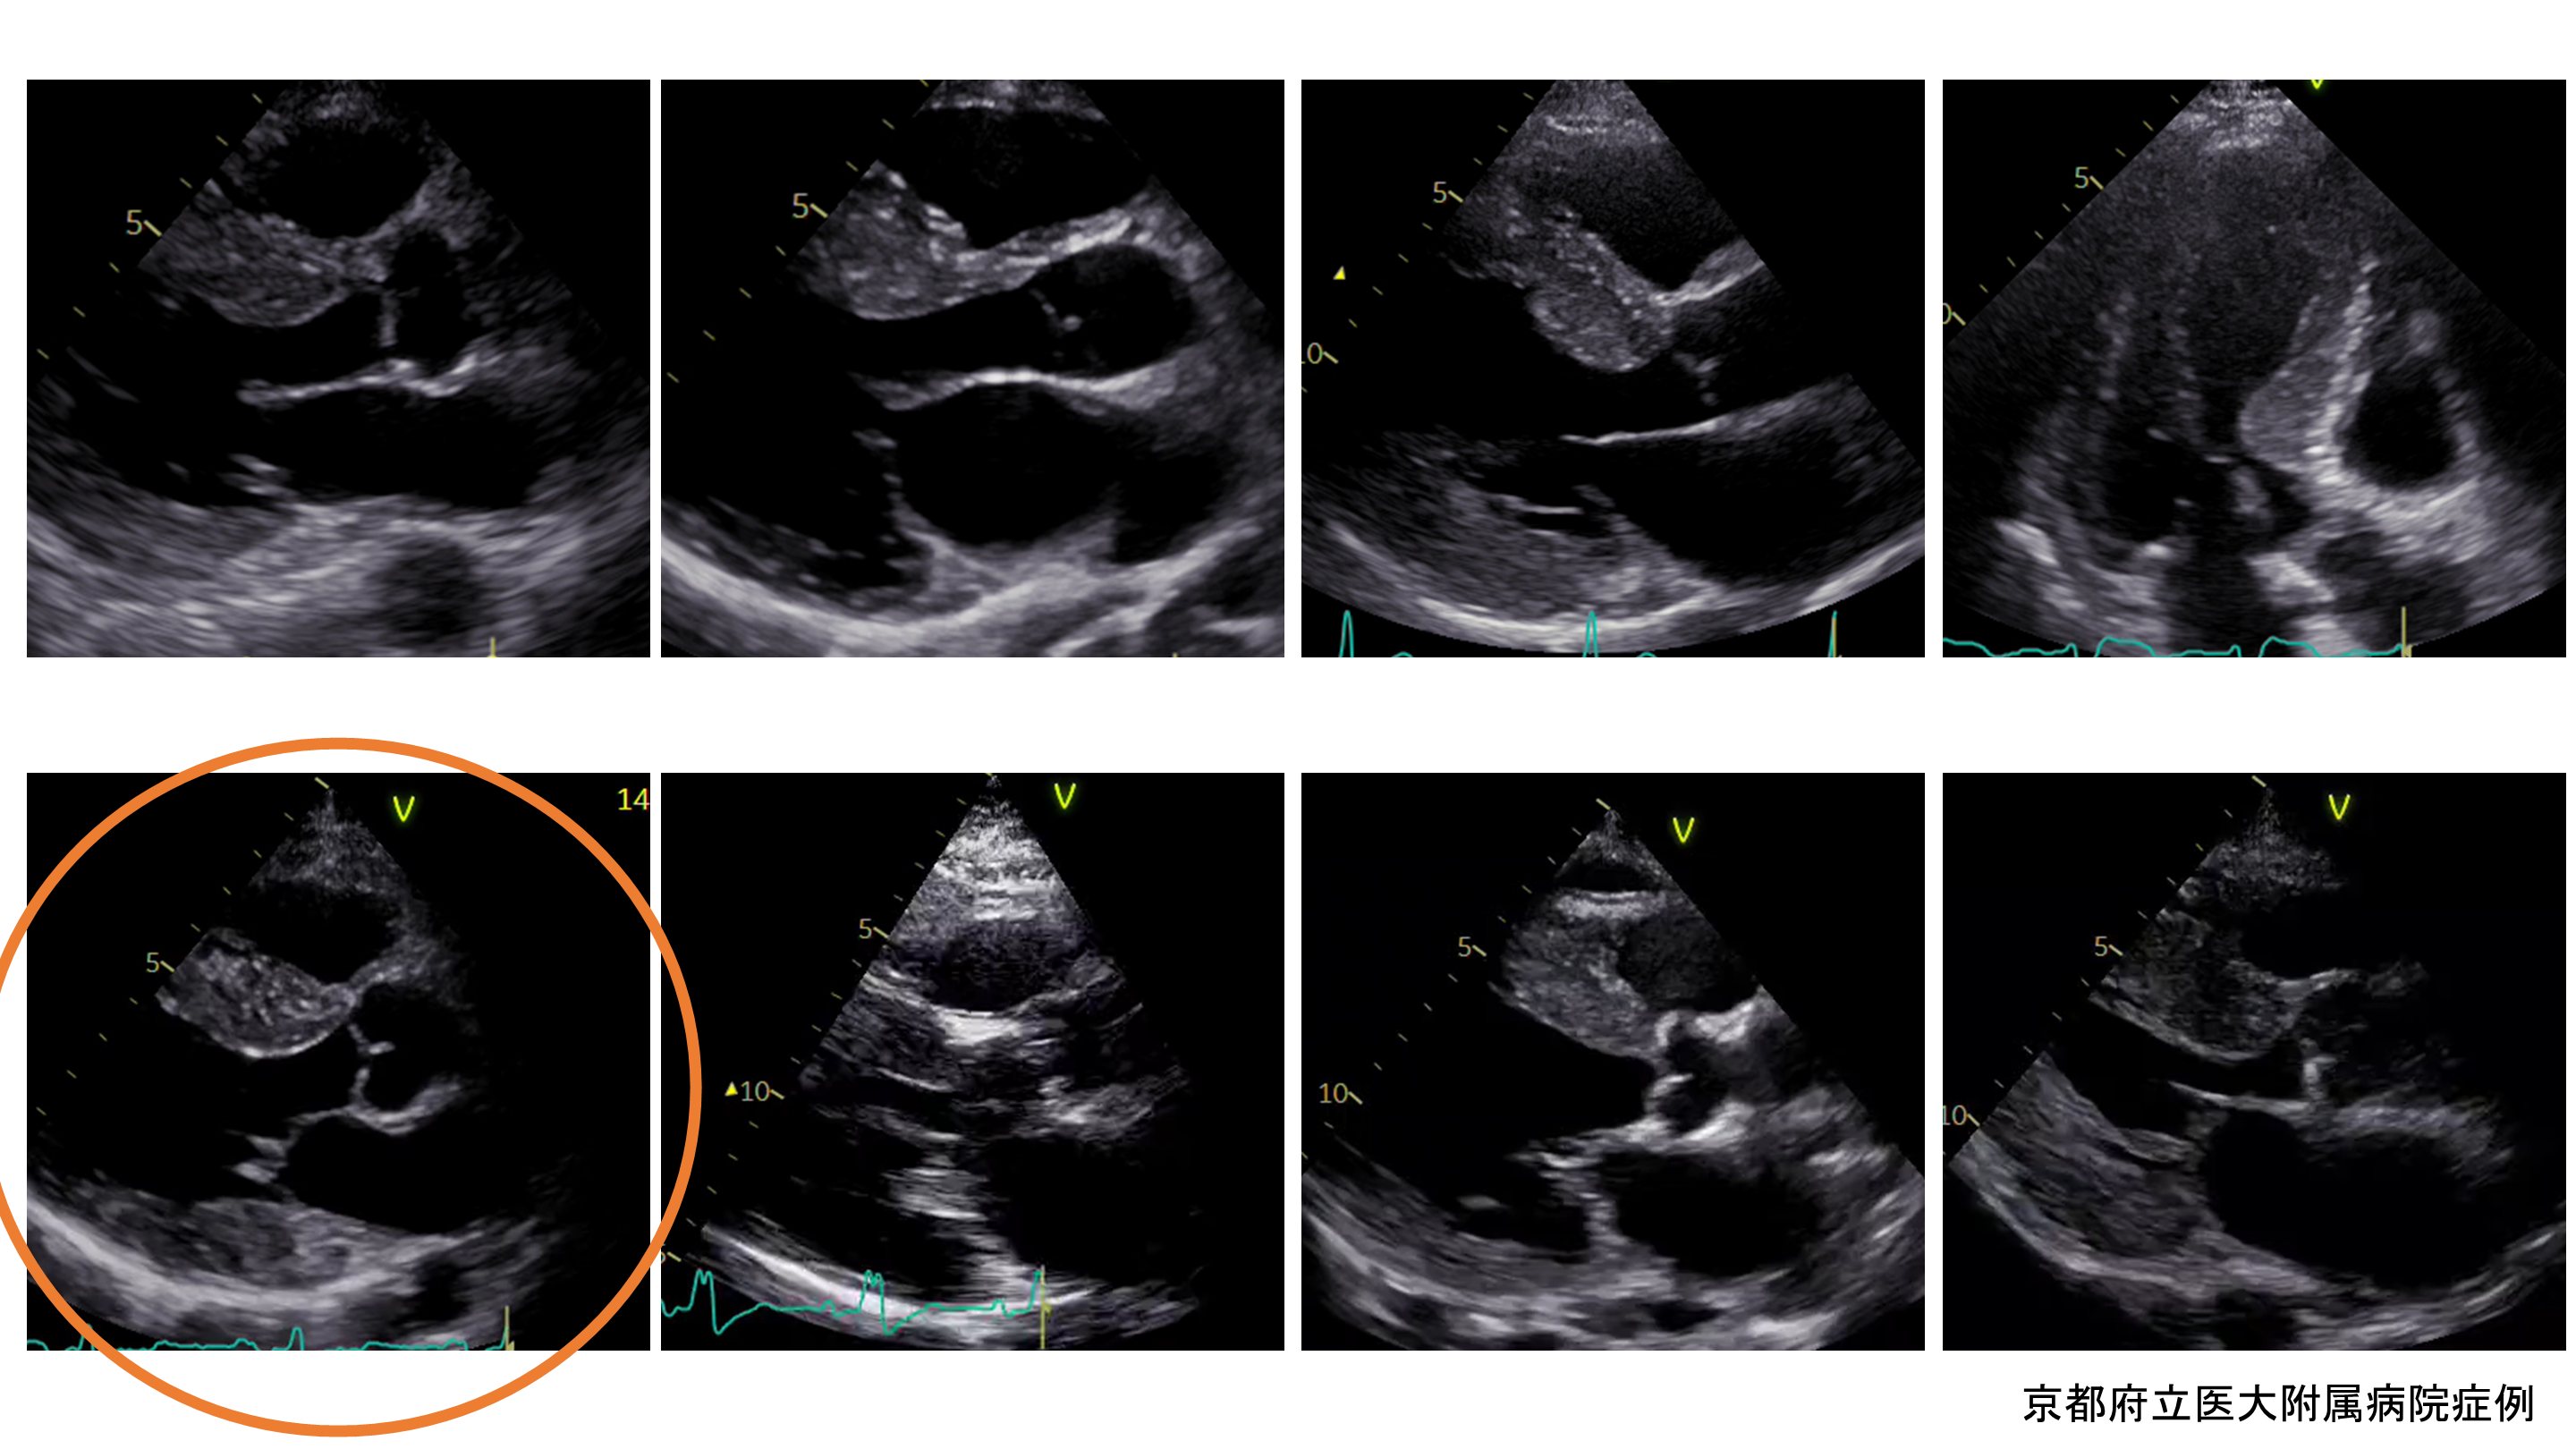

京都府立医大附属病院症例

京都府立医大の症例と肥大型心筋症

心エコー図とLVOTの評価